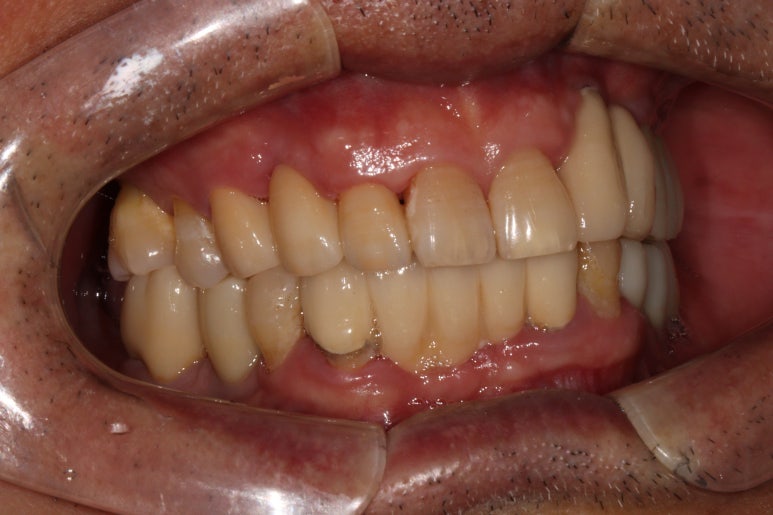

저희 병원에 오셨던 60대 남자 환자분입니다.

딱 봐도 구강위생상태가 좋지 않습니다...

잘 보시면 적절히 관리되지 않아 다수 축적되어있는 치태와 치석들을 쉽게 보실 수 있죠.

아~ 잇몸이 좋지 않았습니다. 그래서 스케일링과 잇몸치료 그리고 필요한 치아를 뽑고 임플란트 하기를 권해드렸죠. 이 분이 3년만에 저희 병원에 다시 오셨는데요.

이번에 저희 치과로 오신 이유는 바로 이 송곳니 때문이었습니다.

딱 봐도 만성 치주염이 너무 심해서 고름이 맺혀있는 것을 보실 수 있죠..

이미 병적 치아 이동 상태 (pathologic migration)이 심해서 치아는 내려오고 치아 사이 틈은 더 벌어진 상황.

속된말로 치아가 둥둥 떠있었습니다.

보시면 치아의 병적 이동으로 이미 자기 자리에서 한참 이탈해버린 오른쪽 위 송곳니를 보실 수 있습니다.